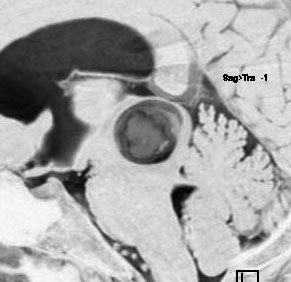

小さな松果体奇形腫です。

OTAでこの奇形腫を見ようとする場合に,テントを静脈洞交会の低い位置まで切断しなければ,直静脈洞の横から松果体部をみることはできません。また,黄色の矢印の方向に視野が入るので,まず最初に邪魔になるのは小脳上極です。上小脳層を左右ともに十分剥離すると,小脳が可動化して,その向こうに,precentral cerebellar veinが見えます。このveinをガレン大静脈への流入部から小脳前面に沿って剥離していくと,小脳上極がさらに可動化して松果体への視野が開ます。

松果体腫瘍の手術では,中脳背面を見る必要があります。特に上丘とそれに連続する後交連 posterior commissureを十分に観察するために周囲組織の剥離を行います。具体的には迂回槽と下丘の周囲のクモ膜組織を剥離します。対側中脳と迂回槽を見る時に妨げになるのが,緑の矢印で示した直静脈洞です。テントが長く切断してあって直静脈洞が大脳鎌と一緒に動かせると対側を見るのがとても簡単になります。